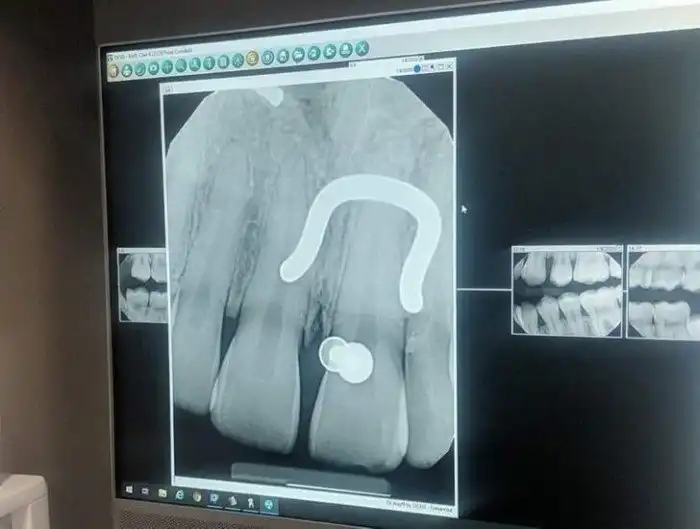

14. "Зубная фея должна мне много денег. Мне 33 года, и вот мои рентгеновские снимки, на которых видны оставшиеся молочные зубы"